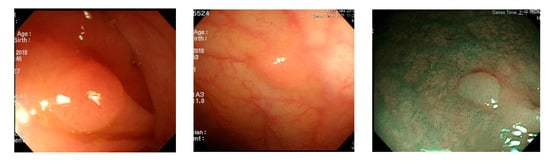

For polyp detection, the mean accuracy of grayscale images was 95.1%, which was higher than that of RGB/NBI images (94.1%). Detection errors in RGB images were caused when polyp protrusions were nonobvious or had a texture similar to that of the intestinal wall (Figure 13), images had excessive noise (Figure 14), or the polyps had an excessively small pixel size (Figure 15). Particularly, polyps with a size less than 1600 pixels (40 × 40 pixels) in the image were likely to be misjudged. Therefore, we recommend that in polyp detection, the length and width of polyp images must be at least 40 pixels in the lens regardless of the actual size of the polyps. This is likely to reduce misjudgment. We also found that when the colorectal polyps image is more complex, such as with more wrinkles or light spots, the use of color image deep learning for polyp detection may be more accurate. In addition, when the vascular lines of colorectal polyps were less obvious, such as unfocused or residual images, it would be better to use gray-scale image deep learning for polyp detection. Next step we plan to use a hybrid deep learning model that combines color and grayscale images for polyp detection in the dynamic colonoscopy videos. Maybe it can take the advantages of both methods as well as improve the detection accuracy.

Figure 13.

Nonobvious polyp protrusions or similar to intestinal wall.

Figure 14.

Excessive noise images.

Figure 15.

Small pixel size polyp images.

In polyp classification, neoplastic polyps were likely to be misjudged as hyperplastic polyps when polyp textures were not obvious (Figure 16), images had an excessively low resolution, or when polyps were smaller than 1800 pixels (Figure 17). Hyperplastic polyps, however, were likely to be misjudged as neoplastic polyps because of the WL around polyps in the images and when polyps were smaller than 1800 pixels.

Figure 16.

Unobvious polyp textures.

Figure 17.

Polyp image size below 1800 pixels.